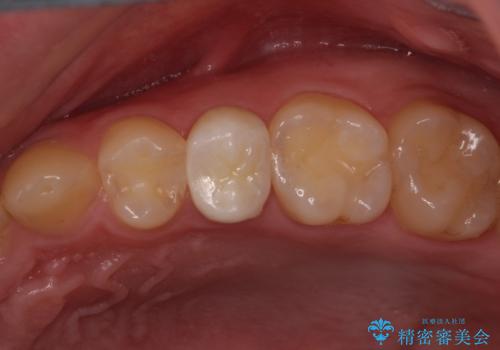

- 「左右どちらとも、どこかが痛む」とご来院された患者様です。

他院で虫歯治療を複数行っており、原因となりうる歯がいくつかありました。まずレントゲン上最もあやしい右上から治療開始しました。右上の歯は1本割れていたため、部分矯正で引っ張り出しました。

右上もう1本と左上は虫歯治療(セラミックインレー、セラミッククラウン)を行いました。

他院で虫歯治療を複数行っており、原因となりうる歯がいくつかありました。まずレントゲン上最もあやしい右上から治療開始しました。

右上の被せものを除去したところ、中で歯が割れていたため、部分矯正で引っ張り出すことになりました。

歯を引っ張り出したり、歯肉の手術の経過待ちの間に、患者様のご希望で他の歯の虫歯治療も行いました。